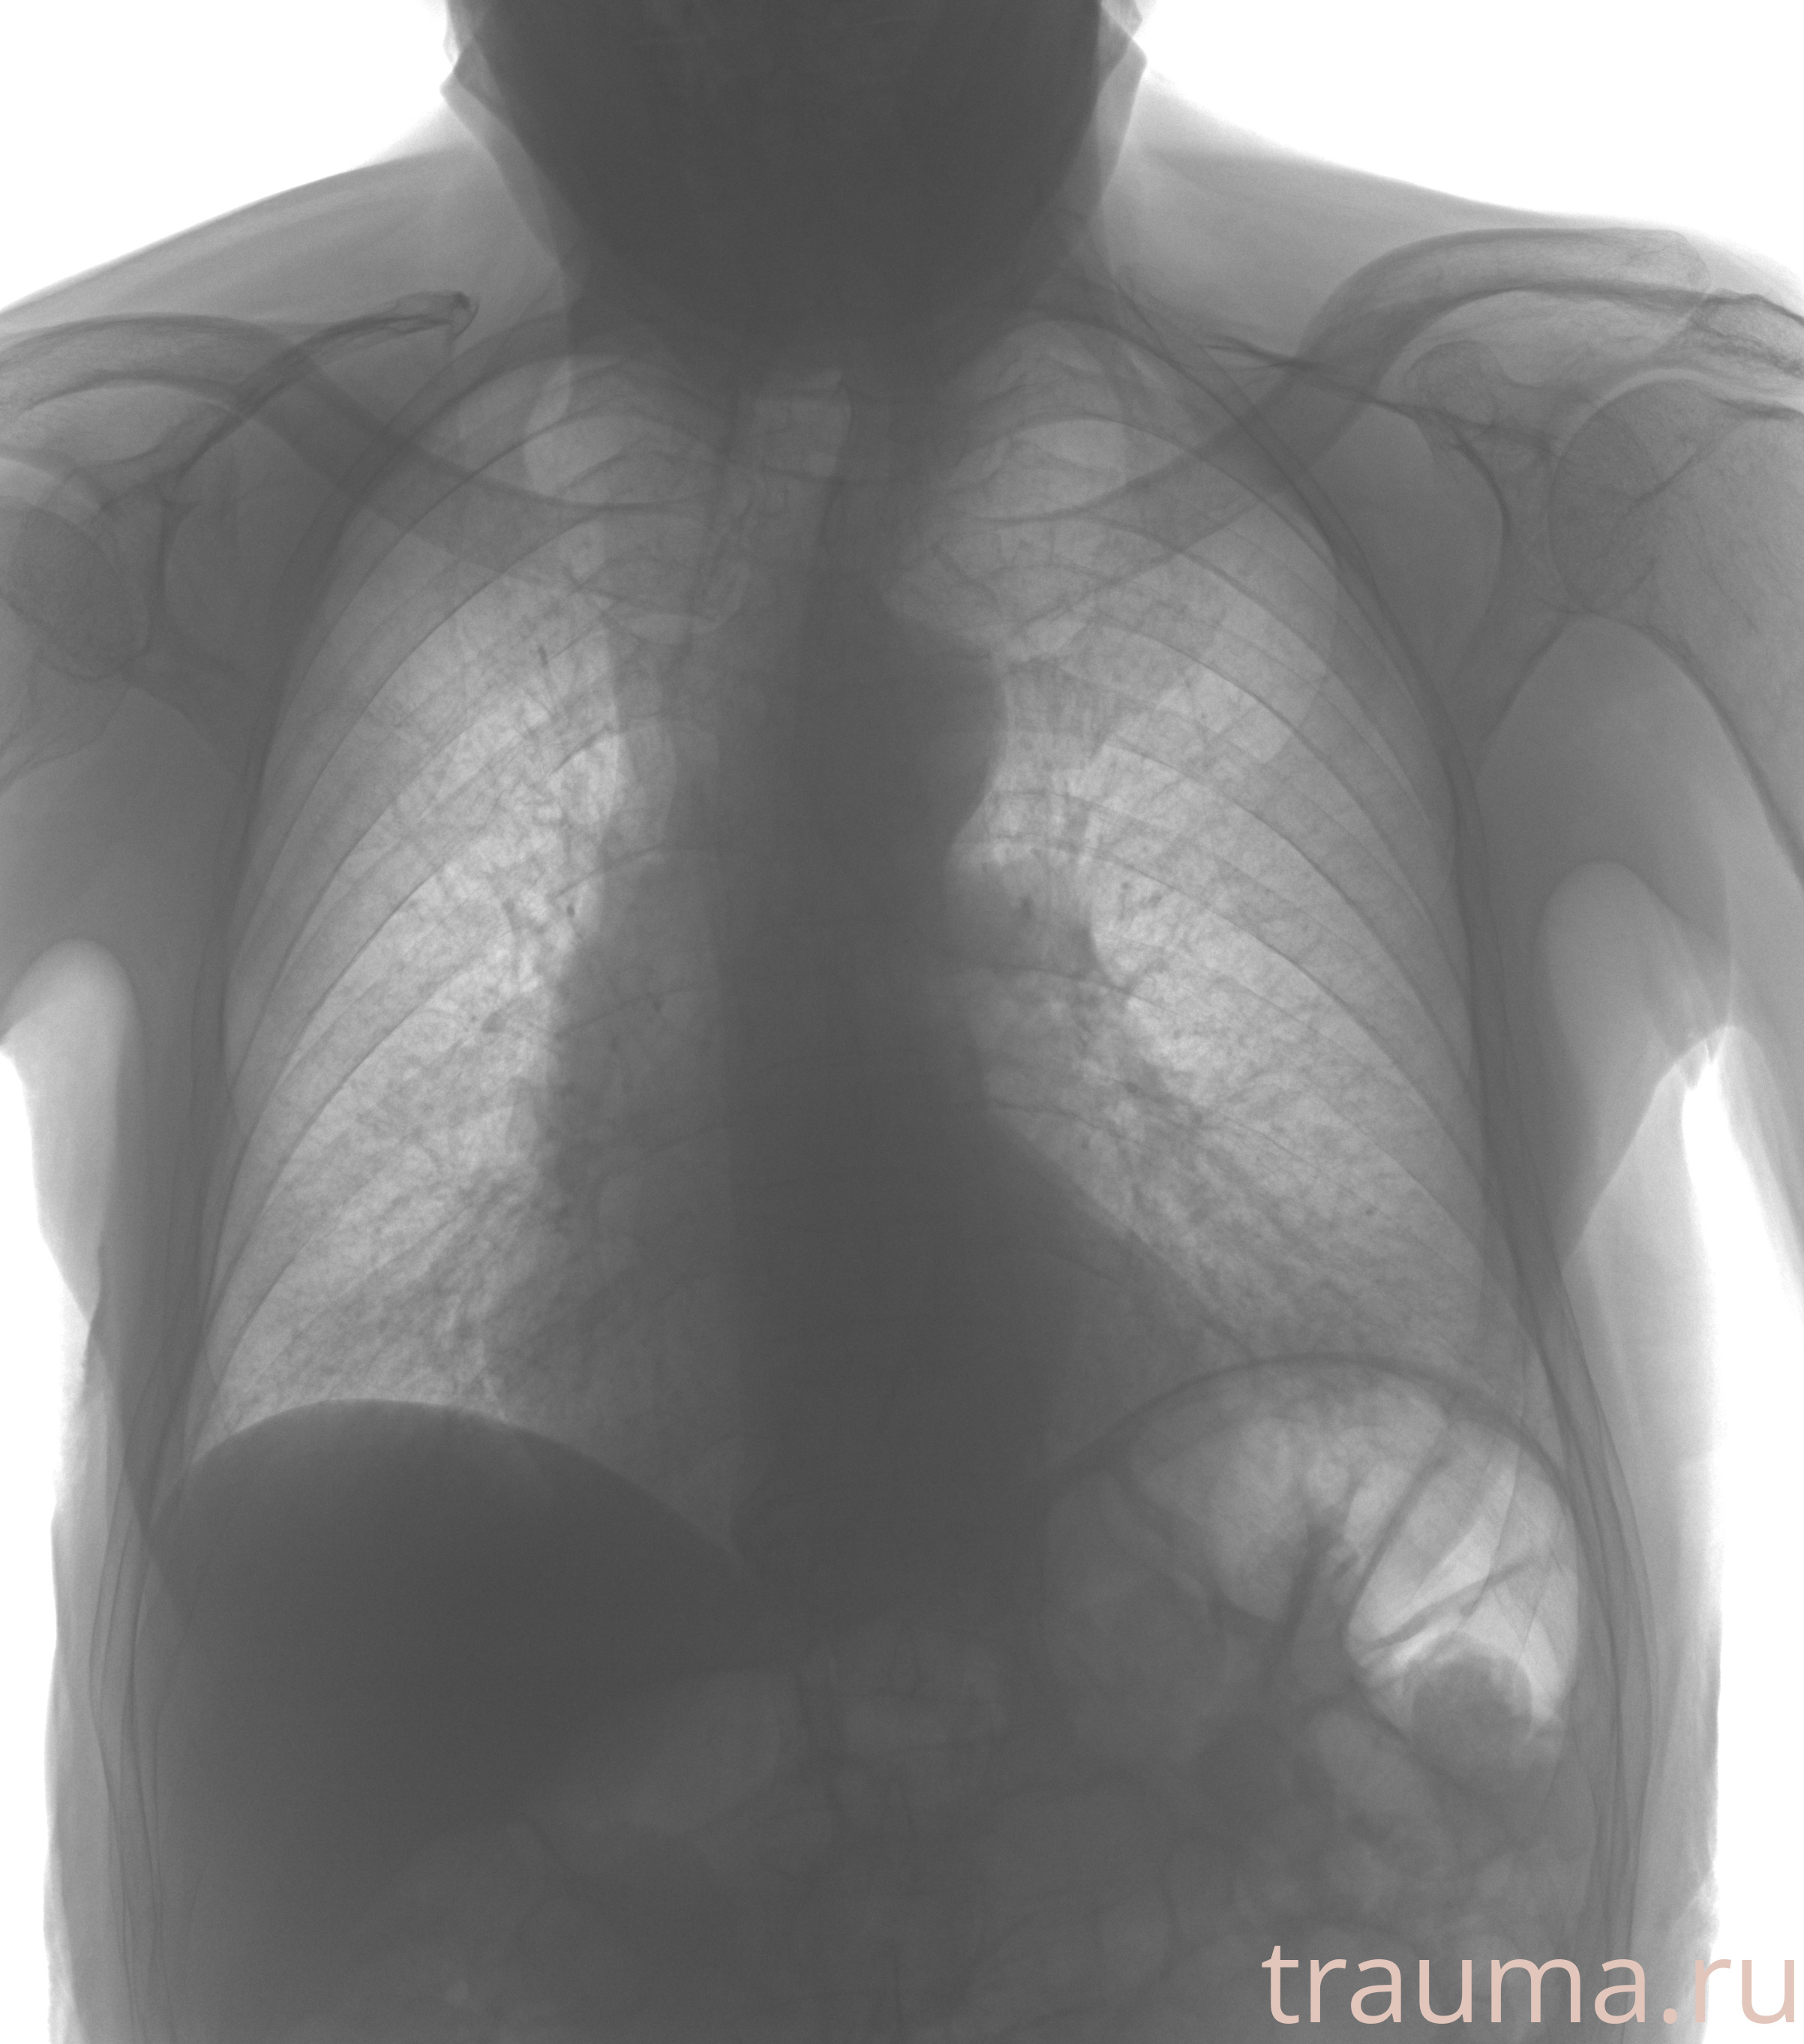

Рентгенограммы

Рентген на дому: по вашему адресу приезжает врач-рентгенолог, травматолог-ортопед с мобильным рентгеновским аппаратом, проводит диагностику травмы или заболевания, делает необходимые рентгенограммы, дает рекомендации по дальнейшему лечению. Получить качественные снимки в домашних условиях возможно благодаря уникальной методике, разработанной МосРентген Центром для института  Склифосовского